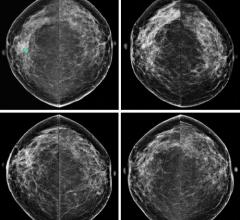

May 15, 2019 — High negative predictive values (NPV) in mammography architectural distortion (AD) without ...

April 6, 2018 — New American College of Radiology (ACR) and Society of Breast Imaging (SBI) breast cancer screening ...

March 29, 2018 — The American College of Radiology (ACR) released new breast cancer screening guidelines recommending ...

February 10, 2017 — A new method for screening women with dense breast tissue may potentially save thousands of lives by ...